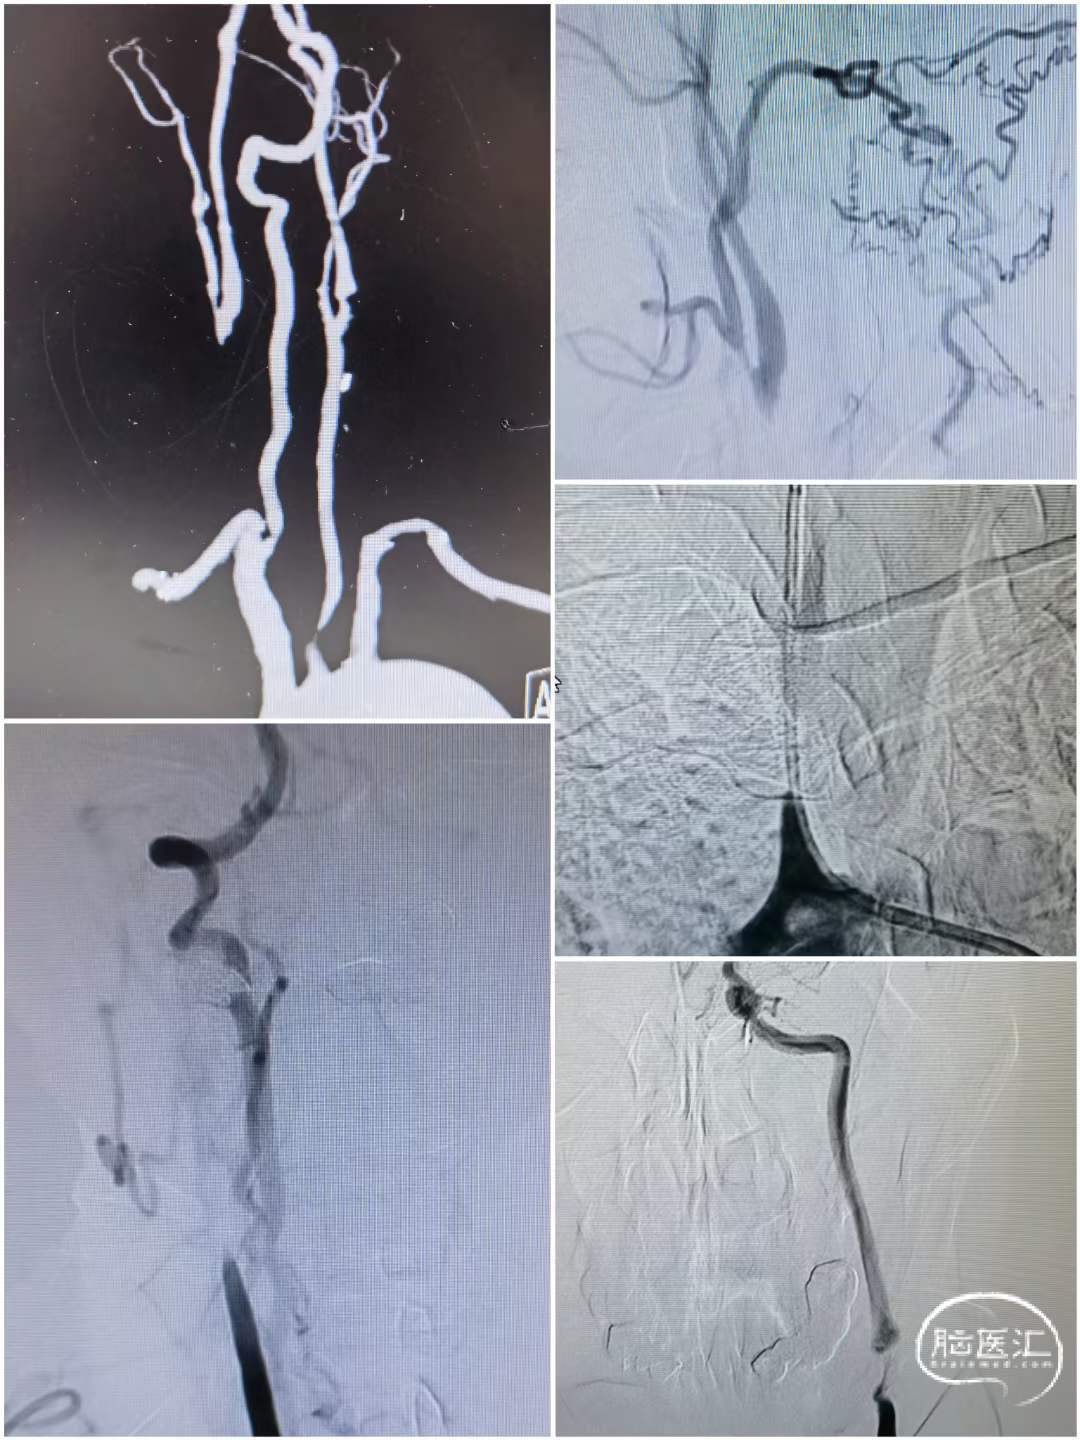

术前造影

造影可见:右侧颈总动脉慢性闭塞,左侧颈内动脉、颈总动脉串联狭窄。